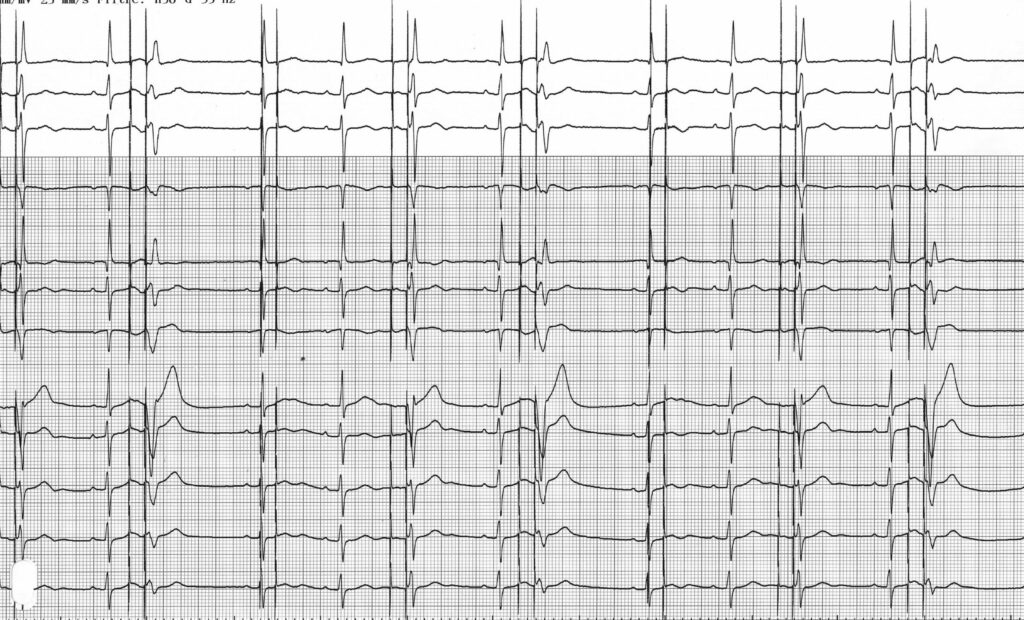

Même patient que tracé précédent; programmation en mode D00

Sur ce tracé, on peut voir une stimulation atriale et ventriculaire régulière à une fréquence de 40 bpm; la capture atriale et ventriculaire n’est effective que quand elle survient en dehors des périodes réfractaires myocardiques (atriales et ventriculaires); cette stimulation est asynchrone, les activités atriales et ventriculaires ne sont pas détectées et ne peuvent donc pas inhiber la stimulation; quand la stimulation ventriculaire survient sur le sommet de l’onde T, on note la présence d’une capture avec un risque arythmogène;

Le fonctionnement du mode D00 est inversé par rapport au mode 0D0: pas de détection possible et stimulation à intervalles fixes. Les modes asynchrones à fréquence fixe étaient les seuls modes disponibles sur les premiers stimulateurs cardiaques. Le mode D00 induit une stimulation atrio-ventriculaire séquentielle asynchrone, sans inhibition par les évènements intrinsèques.

Comme vu sur ce tracé, quand le patient n’est pas dépendant, une parasystolie survient avec compétition entre activités spontanées et activités stimulées. Ce mode permet de vérifier l’efficacité de la stimulation et permet d’éviter l’inhibition en cas d’exposition à une interférence extérieure (bistouri électrique chez un patient dépendant par exemple). La stimulation est efficace et capture l’oreillette ou le ventricule uniquement quand elle survient en dehors de la période réfractaire absolue physiologique qui suit une oreillette ou un ventricule spontané.

Ce tracé montre le risque de ce type de mode. Plusieurs stimulations ventriculaires surviennent au sommet de l’onde T d’un QRS spontané non détecté. Il s’agit de la période vulnérable avec risque d’induction d’un trouble du rythme ventriculaire. Le risque de fibrillation ventriculaire est limité mais augmente en présence d’une ischémie myocardite ou d’un trouble métabolique. De la même façon, une stimulation atriale asynchrone en période vulnérable atriale peut induire un accès de fibrillation auriculaire.

Les EGMs montrent que les signaux atriaux et ventriculaires sont amples mais ne sont pas détectés (mode D00) expliquant la stimulation asynchrone;